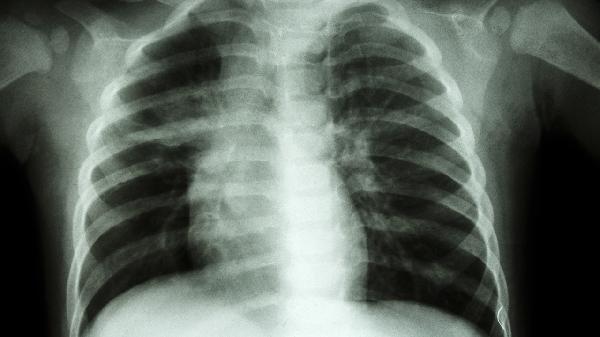

4、胸膜炎:

胸部直接损伤或发生感染会累及胸膜,使局部发生炎症反应后出现右边胸痛的现象,甚至会累及肋骨部位,还可能会伴有胸闷、气短、呼吸困难等。可以在医生指导下服用甲硝唑片、头孢呋辛酯片、罗红霉素胶囊等药物治疗,能够起到抗感染的效果。